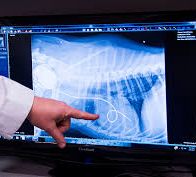

検査法心疾患を診断するために、次のような検査法を用います。病歴の把握:心疾患は、どの家畜においても発見されますが、診療にあたっては、犬にもっとも多く見られます。先天性心疾患の場合は、一般に発育が悪く元気の良くないものが多い。また心内雑音が聞...